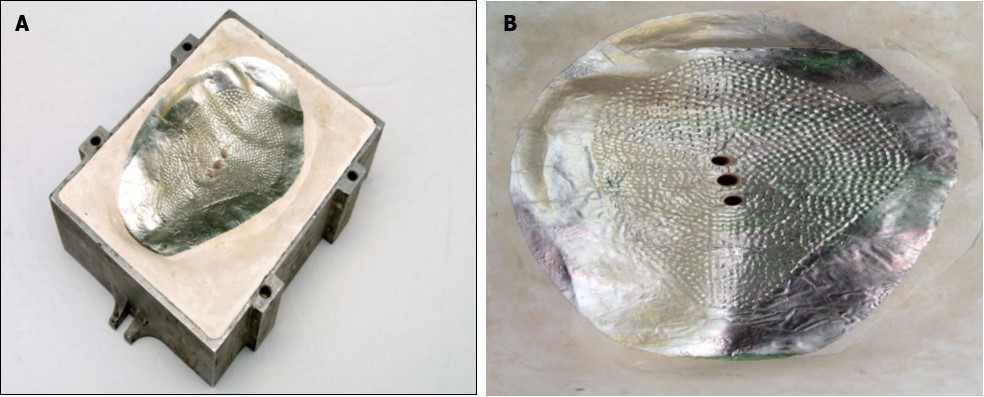

Once the wax model shape was finalised, a two-part mould was made in Crystacal® gypsum (Saint-Gobain Formula, Kutzhütte, Germany). The mould was made in a two-part metal flask to allow the silicone to be pressed under pressure without cracking or fracture of the plaster. The wax model was placed in wet plaster, smoothed and allowed to set, then separated using a separating medium such as Vaseline® (Unilever, London, United Kingdom), or Medi Mould (Polymed Limited, Cardiff, United Kingdom). The top half of the flask was filled with plaster. The flask was boiled to remove the wax (lost wax technique), leaving a plaster relief of the implant. The plaster surface was roughened with a 2mm drill burr in multiple places to discourage capsulation of the prosthesis within the body (Figure 2a and b). The model was separated using Medi Mould to prevent sticking of the plaster to the silicone.

Figure 2.a) and b) Mould created in the plaster flask, using the lost wax technique. Holes are present in the surface to roughen the implant and help prevent capsulation.